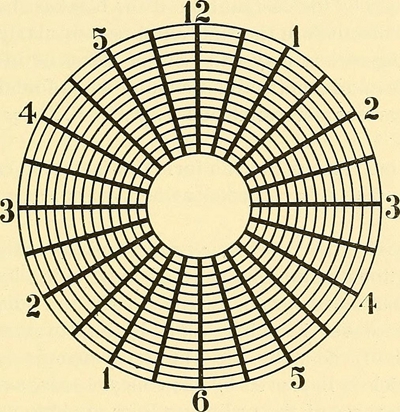

A:判斷自己有沒有散光,最簡單的方法是使用散光表來測試。散光表是一種簡單、方便的方法,但是它的準確度不是特別精確。在配鏡的情況下一般再用裂隙法,或者是交叉圓柱鏡法來精調散光的度數。散光表在網上可以看到,它類似於鐘錶的盤面,有12個數字。各個鏡線……